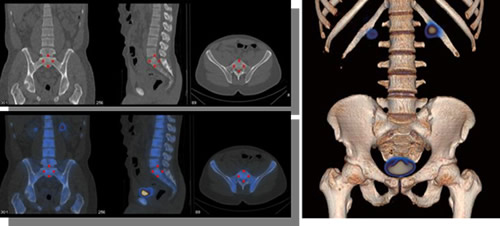

臨床的には,がんの骨転移や軟部腫瘍,心疾患などのより詳しい診断,ならびにこれまで呼吸による影響を受けやすかった胸腹部の診断に貢献することを目指している(下図参照)。

Optima NM/CT 640の撮影画像(実効線量:1.13mSv)

Courtesy of Dr. Ph. Declerck, Clinic Saint Jean, Belgium

重ね合わせ画像は核医学データ処理装置「GENIE-Xeleris」(薬事承認番号:20700BZY00161000)にて実施